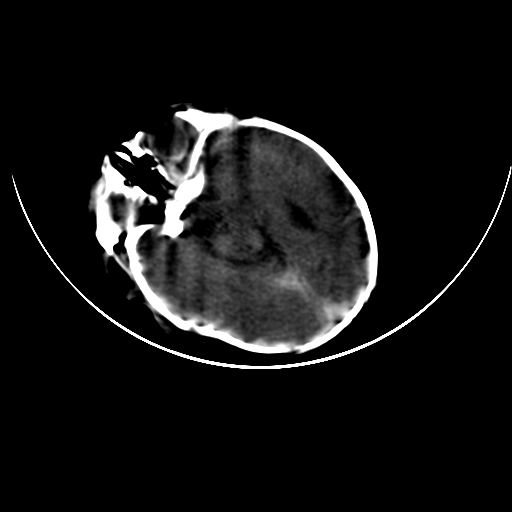

双侧硬膜下血肿并蛛网膜下腔出血。

双侧硬膜下血肿并蛛网膜下腔出血

硬膜下及蛛网膜下腔出血。

hie 蛛网膜下腔出血,硬膜下血肿。

hie;双侧硬膜下血肿并蛛网膜下腔出血

双侧硬膜下血肿并蛛网膜下腔出血,考虑维生素k缺乏引起.

较大范围出血,应考虑维生素k缺乏引起,结合临床吧。